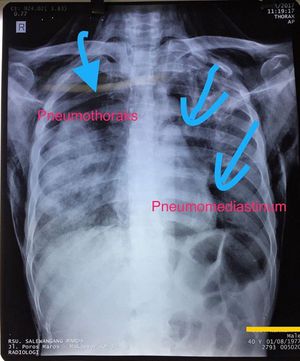

Pneumothorax and pneumomediastinum